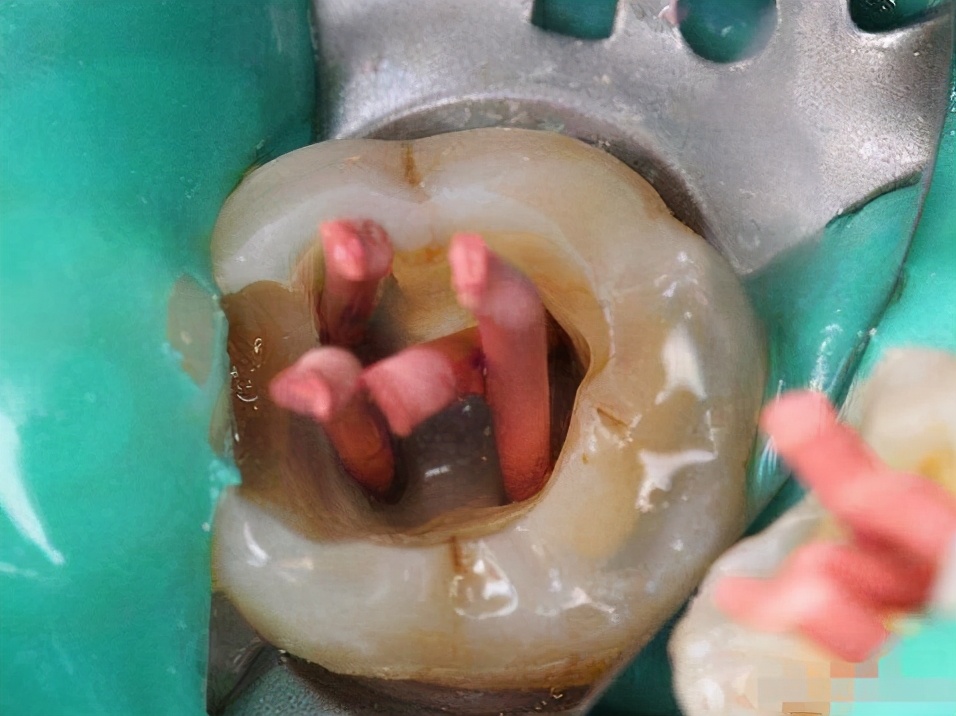

牙髓炎治疗,通常会先开髓减压,用温盐水冲洗消炎、敷药镇痛,暂缓牙疼。后续的治疗中,医生会根据每个人的牙齿情况采取不同的治疗方法。

另外,轻度牙髓炎患者,目前治疗方法有直接盖髓术、间接盖髓术和牙髓切断术,目的是以保留活髓与牙齿为主,去除受感染部位。而重度患者则会采取根管治疗,去除牙髓,做冠修复,最后要视情况确定是否拔除患牙。